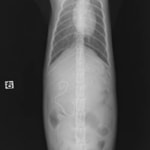

- ・レントゲン検査:胃ガス、腸内ガス陰影、空腸領域に不透過性の陰影あり。

- ・バリウム造影検査:造影後2時間、胃からのバリウム排泄なし。

- 上記検査結果より、同日、内視鏡検査ならびに腸内異物摘出術を実施。

- 内視鏡検査:胃内にて4cm大のロープ様の異物を摘出。胃内、十二指腸内に炎症像が認められた。

◎腸内異物摘出術

本症例は、 おもちゃのロープを誤飲したことにより腸で通過障害を引き起こし、嘔吐として症状が認められた。現在のところ、一般状態に問題なく経過観察を指示。